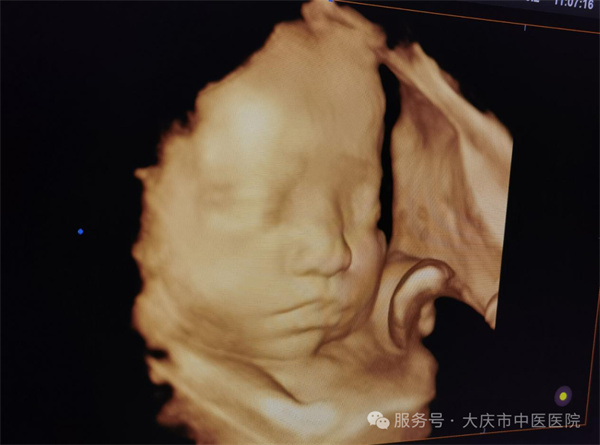

近日,大庆市中医医院超声医学科通过四维彩超筛查,为一位准妈妈做出了及时准确的胎儿发育健康提示。该孕妇为第二次妊娠,曾孕育一健康女孩,现孕23周,在超声医学科进行胎儿系统筛查时,当日值班医生,超声医学科副主任王双艳,经过一番认真细致的检查,发现胎儿存在左侧三度唇裂伴左侧牙槽突裂,其余胎儿结构未见异常。随即向孕妇及家属详细介绍唇腭裂的类型、程度及可能对胎儿出生后的影响,如影响外貌、进食、发音等,同时说明不同程度唇腭裂的治疗方法和预后情况,让孕妇对胎儿病情有全面、客观的认识。最后孕妇决定继续妊娠,足月剖产后证实了产前的诊断。截至目前超声医学科已诊断各型唇腭裂5例,均得到产后证实。

生育一个健康的宝宝是准妈妈们的最大心愿!因此四维彩超筛查十分必要。通过系统超声检查能够清晰显示胎儿颜面部的形态结构,可以实时动态观察到唇部和腭部的连续性,能直观呈现唇腭裂的部位、程度等情况,并且能清晰显示唇裂是单侧还是双侧,裂隙的大小等。让医生和家庭提前知晓胎儿情况,为是否继续妊娠等决策提供关键依据。有助于减少严重出生缺陷儿的出生,提高人口素质。 若确诊唇腭裂,医生可结合其他因素综合评估,为产妇选择更合适的分娩方式,保障分娩过程中母婴安全。诊断结果能协助临床相关科室制定出生后治疗计划,确保患儿出生后能及时得到多学科综合治疗。

大庆市中医医院四维彩超设备,为三星WS80A彩超诊断系统,具有极高的清晰度和分辨率。能360°全方位立体呈现胎儿表面畸形、内脏畸形和头面部畸形及宫内发育情况,如胎儿孕周、体重大小,预产期的估测,脐带血流及胎儿宫内缺氧的评估等,还有子宫动脉的超声评估,是应用于胎儿产前筛查、及完整记录胎儿宫内高清动态的先进超声设备。超声医学科以规范化的胎儿系统筛查标准服务于广大孕产妇,严格做到标准、规范、细致、认真。在此也提醒准妈妈们,要重视产前超声检查,以超声之“眼”,为“好孕”护航。